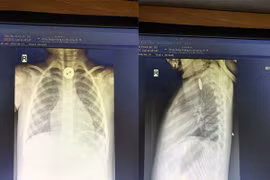

Trẻ hóc cúc áo vào đường thở

(khoahocdoisong.vn) - Dị vật đường thở là những chất vô cơ hay hữu cơ mắc vào thanh quản, khí quản hoặc phế quản gây nguy hiểm tính mạng nếu không được cấp cứu kịp thời.